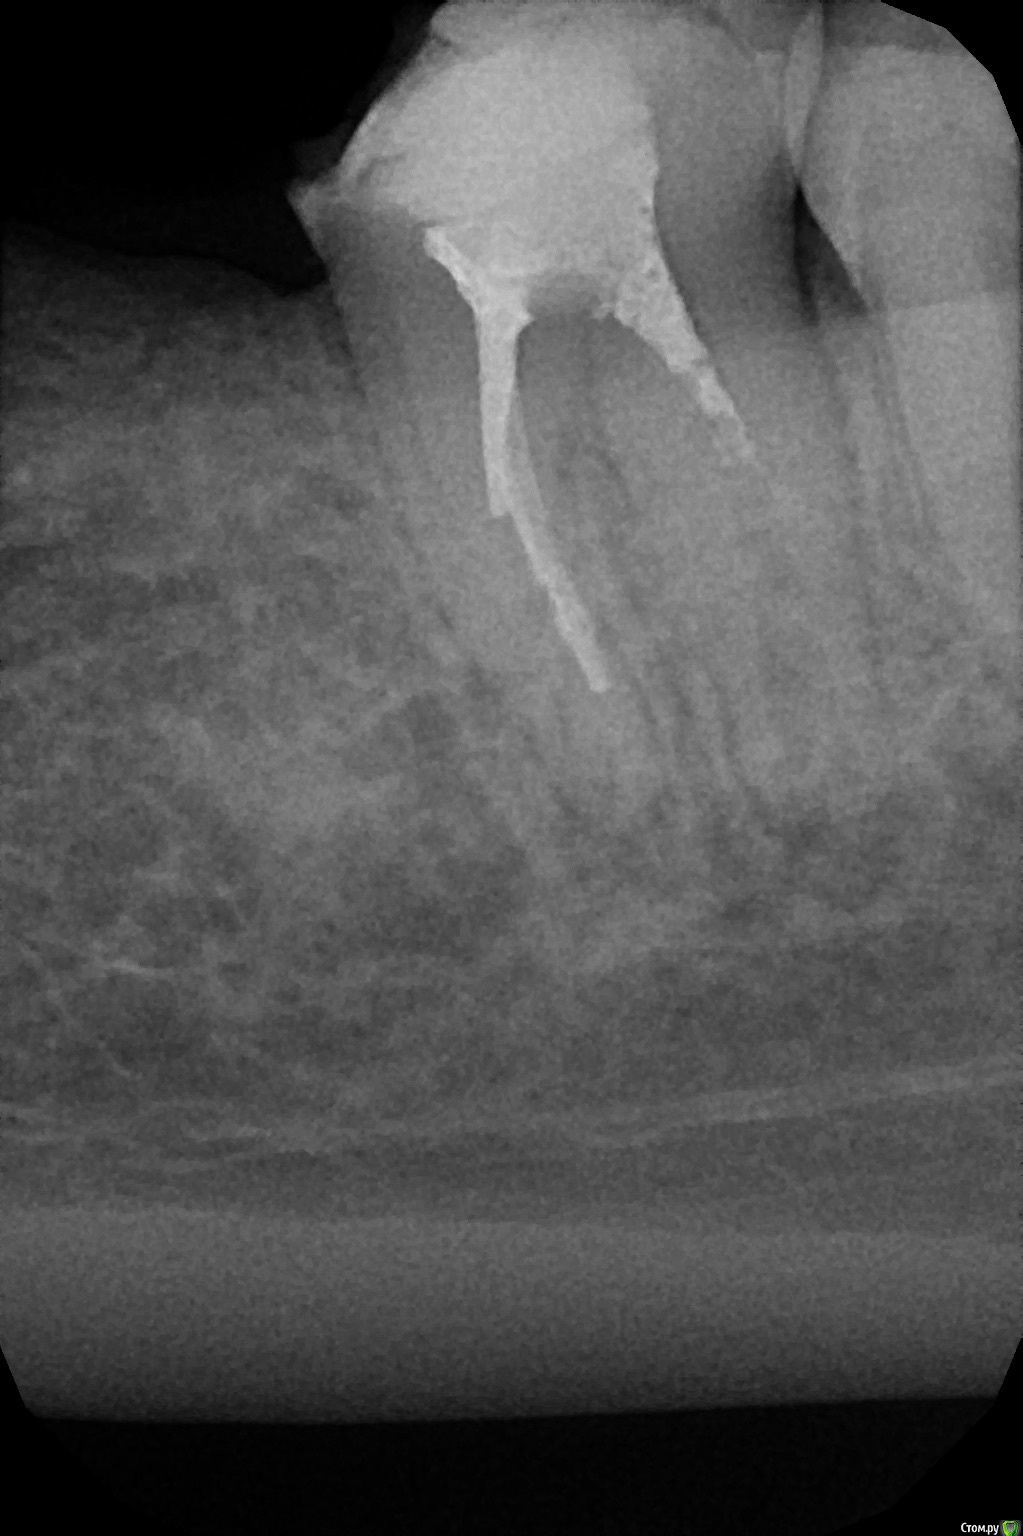

marialera Опубликовано 24 сентября, 2015 Поделиться Опубликовано 24 сентября, 2015 Здравствуйте,уважаемые коллеги.У кого какое мнение будет по анатомическому строению данного зуба и по его плану лечения.Пациент ранее лечил этот(37) зуб в другой клинике,но по некоторым обстоятельствам продолжить там лечение не может.В каналах метапаста. Боль отсутствует.Зуб вообще не беспокоит.При прохождении каналов под анестезией (по словам пациента) была иногда острая боль. Ссылка на комментарий

marialera Опубликовано 24 сентября, 2015 Автор Поделиться Опубликовано 24 сентября, 2015 Обычный план. Нормальная изоляция, очистка каналов, я бы повторно гидроокись пложил. Не метапасту, что-нибудь на воде. Дистальный с МТА в апекс, остальные с гуттаперчей и силером. Билд-ап, протезирование.У меня такое впечатление,что дистальный канал раздвоен.Зуб еще не вскрывали.Пока только снимок.пациент записан на завтра Ссылка на комментарий

Brigita Опубликовано 25 сентября, 2015 Поделиться Опубликовано 25 сентября, 2015 мне кажется резорбция на фоне длительного действия гидроокиси, не стала бы ее продолжать.Лечить как обычно,как колчанов советует Ссылка на комментарий

Kolchanov Опубликовано 25 сентября, 2015 Поделиться Опубликовано 25 сентября, 2015 Я бы больше за возможную ступень в мезиальном переживал. Ссылка на комментарий

marialera Опубликовано 27 сентября, 2015 Автор Поделиться Опубликовано 27 сентября, 2015 мне кажется резорбция на фоне длительного действия гидроокиси, не стала бы ее продолжать.Лечить как обычно,как колчанов советуетСняли временную пломбу,вдистальный канал легко входит файл 80 размера и кровит. Ссылка на комментарий